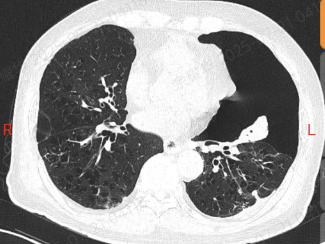

他这肺就像个漏气的气球,气胸反反复复,隔几周就得住院抽气、插管子,CT 片上的肺大疱密密麻麻,医生说这是难治性气胸,传统手术风险不小。

手术前,团队用 3D 成像把病灶看得清清楚楚。

进了手术室,高清胸腔镜像 “放大镜” 一样找到漏口,医生精准修补后,又用上可吸收的生物材料 “补丁”,最后注入自体血促进恢复。